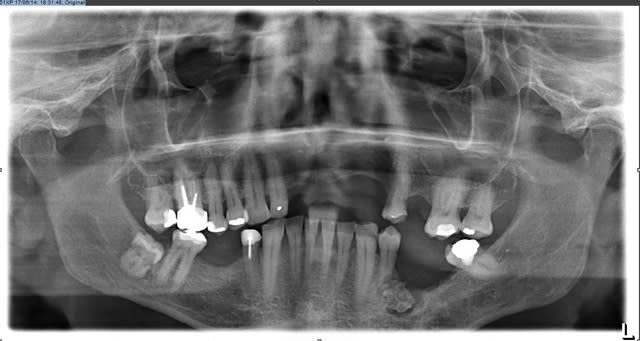

Bonjour à tous je viens de réaliser une pano sur ce patient(qui est en plus un proche)

Que pensez vous de la lésion en regard de la 34, elle n'est pas douloureuse à la palpation, mais lors d'une pression sur la gencive en regard on a un écoulement purulent assez infecte.

pano de controle et là c'est le drame, j'ai alors fait une rétro et il me semble que la 34 n'est pas en cause, de plus elle répond au test au froid.

je l'ai envoyé d'urgence chez un stomato disponible demain mais je me pose pleins de questions sur l'éventualité d'une malignité de cette lésion? D'autant plus qu'elle a l'air en contact avec le trou mentonier?

Pas de critères pour le moment dans le sens d'une malignité.

Préservation du mentonnier pour le moment.